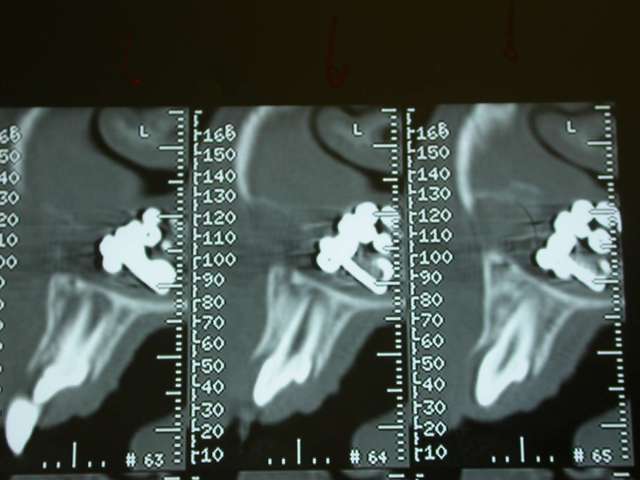

l'objet: une petite chainette boule métallique (celles qui sont accrochées à certains vetements et qu'on retrouve sur les bouchons de baignoire) complétement oxydée (noir de chez noir, avec diminution du diametre de certaines boules) .

temps de séjour estimé dans les fn: 4-5 ans

Je décide donc de faire réaliser un scanner et là c’est nouveau pour vous.

Une fois le scanner réalisé, je vois bien qu’il s’agit d’un objet composé de boules et l’adresse illico à son orl. Il la reçoit dans la foulée, et au vu du scanner, se refuse d’intervenir de peur de renvoyer plus loin l’objet. A son tour, il l’adresse à un hopital spécialisé enfants (Robert Debré). Au service ORL, ils tentent de retirer l’objet avec une pince (comme Dr House le faisait dans un épisode) et rien de neuf, aucune progression.

L’ORL qui s’occupe de Zoe est têtu et tente un dernier coup, en branchant une aspiration chirurgicale hyperpuissante et en couplant l’action de celle-ci avec la pince de House. Et petit à petit, il arrive à sortir cette fameuse chainette. Le tout sans anesthésie.